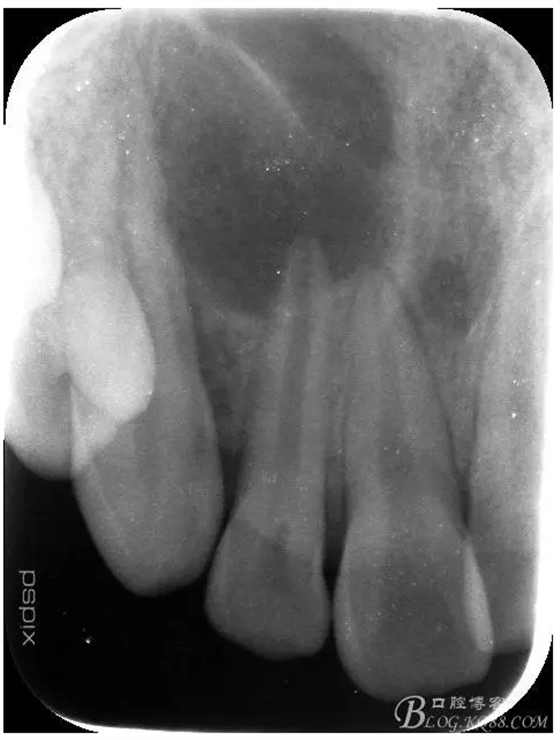

患者、宋xx,男、16歲。主訴:右側(cè)面部腫脹三天。并自覺(jué)鼻腔溢膿。專(zhuān)科檢查:患者右側(cè)眶下區(qū)腫脹隆起,皮膚未變紅,觸痛不明顯,鼻腔檢查未見(jiàn)瘺口。也無(wú)滲出物流出??趦?nèi)檢查:12牙冠未變色。舌側(cè)有一畸形溝,唇側(cè)前庭溝粘膜紅腫隆起,未見(jiàn) 有瘺道觸診有乒乓感,x線檢查:12根尖孔未徹底發(fā)育完成,根尖有橢圓形陰影,大小如花生米,邊界清楚。診斷:12根尖囊腫。處理建議:建議 1.抗感染治療,控制感染的根尖囊腫。2.感染消退后行12根管治療+手術(shù)摘除囊腫+根管倒充填?;颊咄庵委煼桨?,簽手術(shù)知情同意書(shū)。

1.術(shù)前的根尖片檢查及根管治療影像: